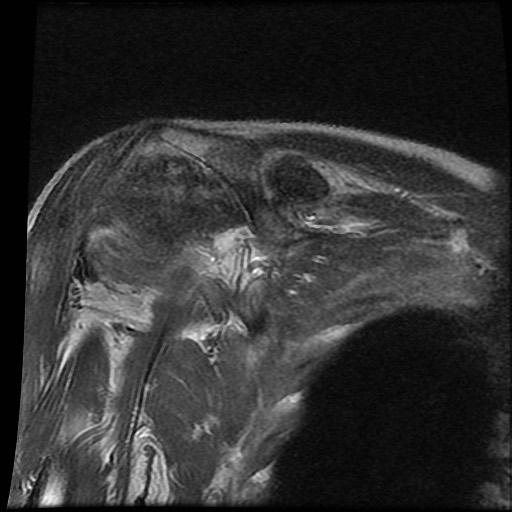

Chuỗi xung T2W

của bệnh nhân bị bệnh khớp do amyloid tại khớp vai.

Các

dấu hiệu bao gồm:

- Sưng nề trong khớp kích thước lớn do

lắng đọng amyloid giảm tín hiệu. - Lan rộng vào khoang dưới mỏm cùng vai và dưới vai.

- Bào mòn lớn tại chỏm xương cánh tay.

Tình trạng sưng nề phần mềm này không nên nhầm lẫn với các hạt cơm (rice bodies) như thấy trong

viêm khớp dạng thấp.